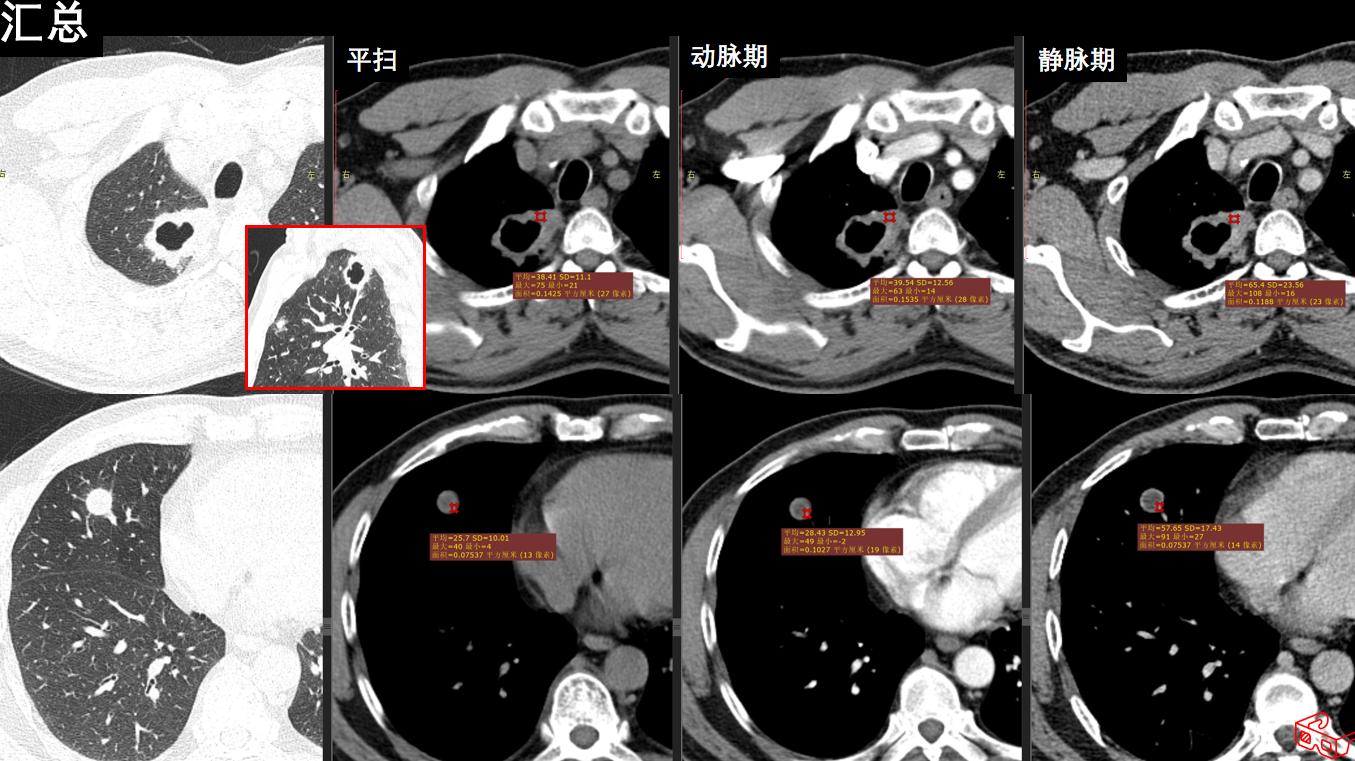

图像:

影像描述:双肺多发结节状密度增高灶,周围可见晕征、毛刺、胸膜牵拉征象,可见空洞样改变,内壁光整,增强轻中度强化,未见淋巴结肿大和胸腔积液。

影像诊断:双肺多发病变(1.真菌感染?2.肺癌?)

病理:肉芽肿性炎。经规范激素+免疫调节治疗后复查,双肺病变明显缩小。

B:影像特点1:双肺多发结节,2部分结节周围可见晕征,3可见空洞,内壁很光整,4未见胸腔积液和淋巴结肿大。空洞的话,中性粒细胞和白细胞不是很高,不考虑金葡菌那种空洞。空洞内壁光整,其余结节周围有晕征,不考虑肺癌并多发转移。结核的话壁薄,卫星灶啊,好发位置啊,病程相对较长,也不考虑。其实隐球菌是不除外的,当然了,一查血管炎自然肯定考虑韦格纳肉芽肿了。这个人做了鼻窦。